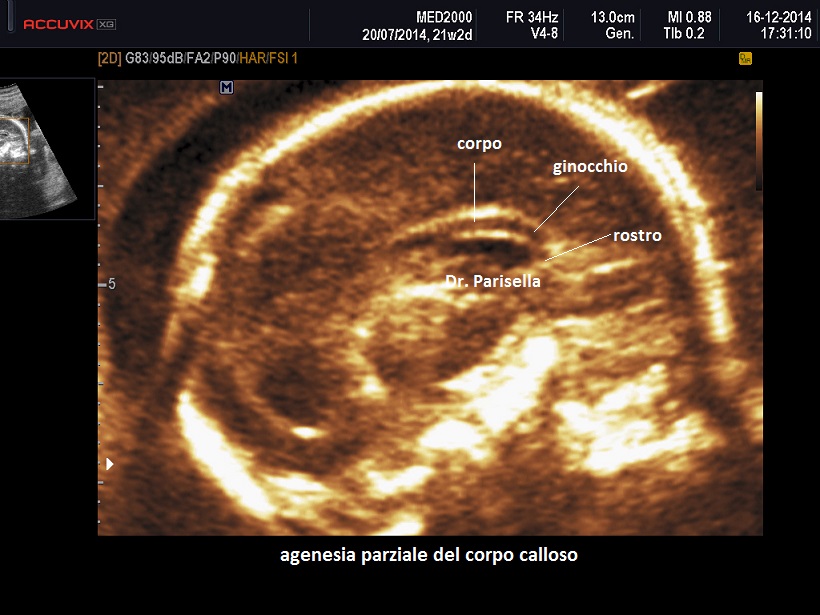

La formazione del corpo calloso avviene proprio in senso antero-posteriore, si forma prima il ginocchio e poi il corpo e lo splenio, per cui le anomalie parziali (disgenesia/ipoplasia) interessano la porzione posteriore del corpo e lo splenio.

In caso di disgenesia/ipoplasia, considerata la formazione in senso antero-posteriore, normalmente manca parte del corpo e lo splenio. In questi casi il cavo del setto che normalmente è situato al disotto del ginocchio è evidenziabile per cui la presenza/assenza non può essere utilizzata come segno indiretto; a volte può essere presente una lieve colpocefalia ma il più delle volte i segni indiretti sono completamente assenti.

La visualizzazione del corpo calloso richiede in genere un piano di scansione sagittale e/o quello coronale; può essere di aiuto la tecnica 3D con la quale partendo dalla sezione per la misurazione della circonferenza cranica è possibile ottenere entrambi i piani, sagittale e coronale.